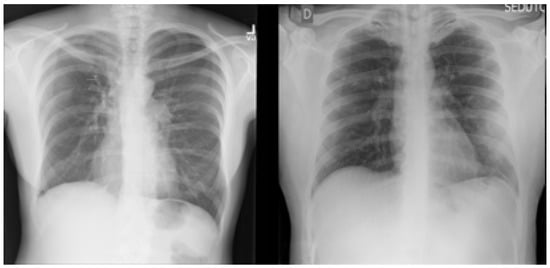

The datasets used in this research were collected from two datasets: the first was from [6], titled “Extensive COVID-19 X-ray and CT Chest Images Dataset” (Available online: https://dx.doi.org/10.17632/8h65ywd2jr.2 (accessed on 25 June 2023 )); the second was from the Kaggle site (Available online: https://www.kaggle.com/paultimothymooney/chest-xray-pneumonia (accessed on 12 June 2023)) that was obtained from [7]. In the collection step, we considered a focus on having a balanced dataset by ensuring that each class comprised almost the same number of X-ray images, each having 5000 X-ray images. Figure 2 shows an example of the collected dataset (X-ray images) with three classes: Normal, COVID-19, and Pneumonia, respectively, from left to right.

For the multi-class classification task used in this research, the dataset consisted of 15,000 X-ray images, labeled with three classes: (1) Normal (which meant that the patient was healthy and was not suffering from any pneumonia type); (2) COVID-19 (which meant that the patient was suffering from pneumonia because of Coronavirus); and (3) Pneumonia (which meant that the patient was suffering from pneumonia because of another type of virus, like SARS). Figure 2 shows an example of the dataset (X-ray images) classes used for multi-class classification tasks: Normal, COVID-19, and Pneumonia, respectively, from left to right.

Figure 2. X-ray images of Normal, COVID-19, and Pneumonia used in binary classification task.